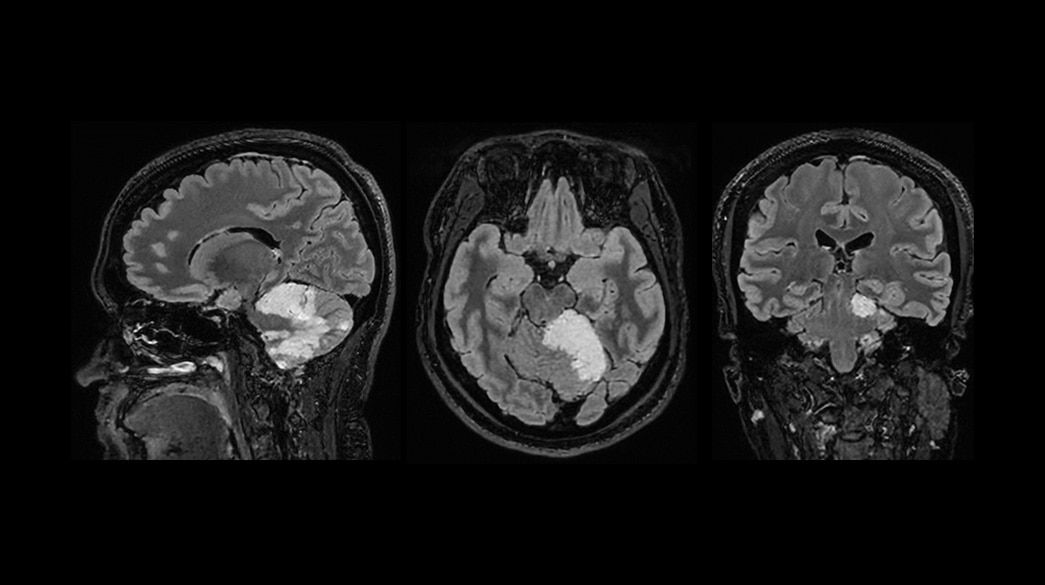

Quantifiable

Provides quantitative and actionable information

Consistent

Motion and distortion-reduced scans with high-resolution and contrast